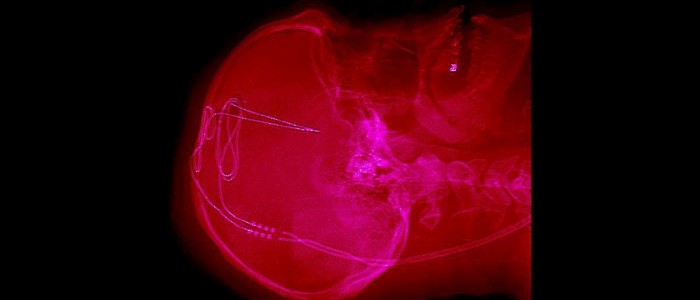

На жаль, жодна з процедур не спрацювала — і саме тому Бакхальтер вирішив дозволити нейрохірурга Алі Резаї просвердлити отвір в його черепі і вживити електрод в його мозок в листопаді.

Електростимулючи частину мозку, яка регулює імпульси, Резаї і його команда з Інституту неврології Рокфеллера Університету Західної Вірджинії думають, що вони зможуть допомогти Бакхальтеру і трьом іншим учасникам нового випробування контролювати їх тягу до опіоїдів.